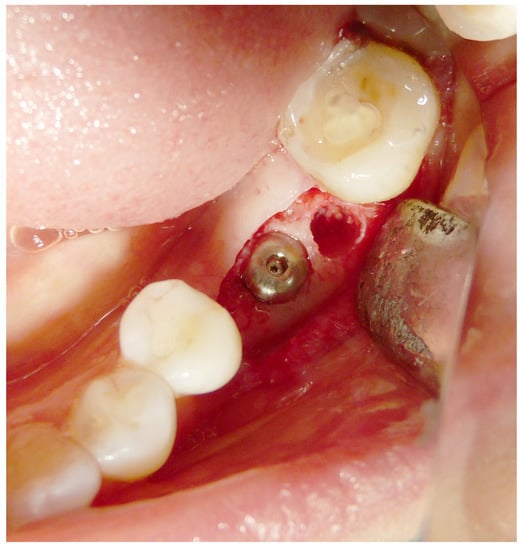

2.4. Surgical Procedures and Follow-Up